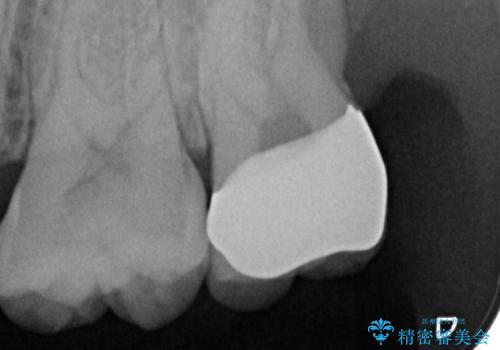

- 銀の詰め物のやり替えを主訴に来院されました。

歯の奥が歯ぐきに埋もれている状態であったため、埋まっている親知らずを抜歯しつつ歯茎の高さを落とし、外れにくいジルコニアクラウンを装着していきます。

- 左上7 歯肉切除:5,500円/仮歯:11,000円/ジルコニアクラウン:110,000円費用は治療当時の料金となります

歯のみでなく歯茎の調整も行うことで、外れにくい被せ物を装着することが可能になります。